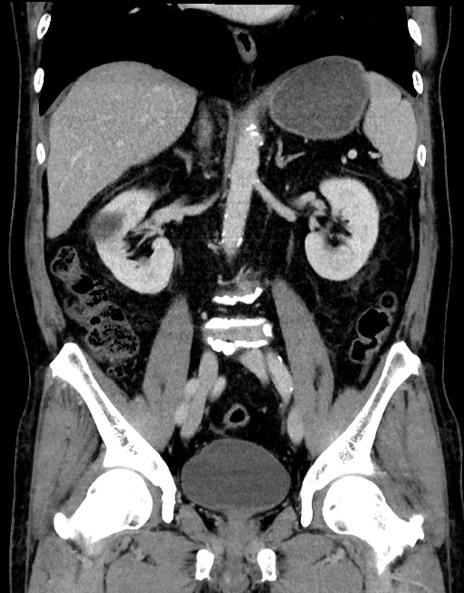

症例15(冠状断像)

【症例】70歳代男性

【主訴】腹痛

【現病歴】今朝から腹痛あり。全体的に痛い。特に左上の方。排ガスが今日はない。冷や汗が出る。

【既往歴】直腸癌術後

【身体所見】左側腹部〜上腹部に圧痛あり。腹膜刺激症状明らかなではない。軽度反跳痛。左下腹部に術後瘢痕あり。

【データ】WBC 7700、CRP 0.02